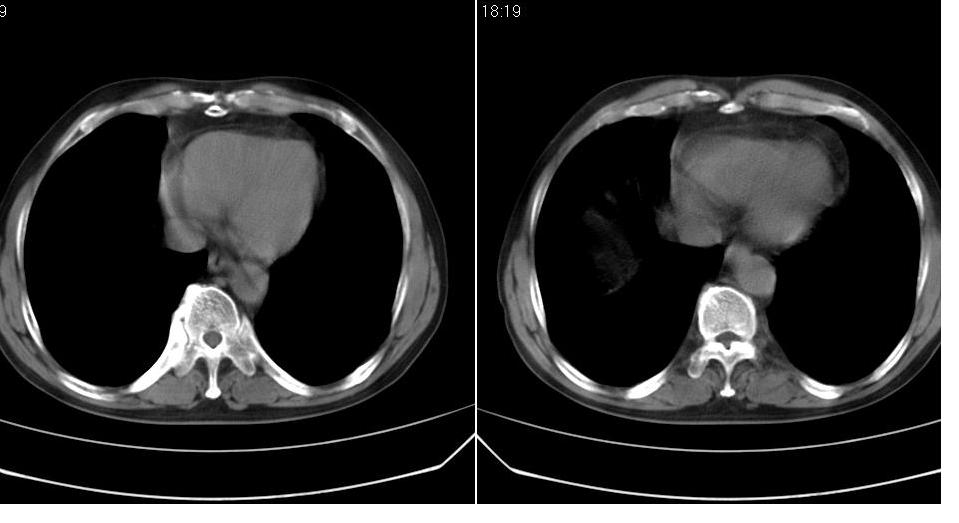

标题: CT19131:男 60岁,咳嗽,喀痰,胸闷,有吸烟史,胸部CT平扫 [打印本页]

男 60岁,咳嗽,喀痰,胸闷,有吸烟史,正常图片未上传,请谅解。

考虑肺癌建议强化